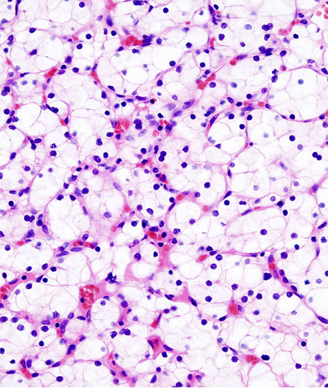

The results of the study comparing Aveo’s tivozanib to sorafenib for the treatment of metastatic renal cell carcinoma showed no improvement in overall survival, the basis for the FDA’s rejection of the company’s new drug application earlier this year.